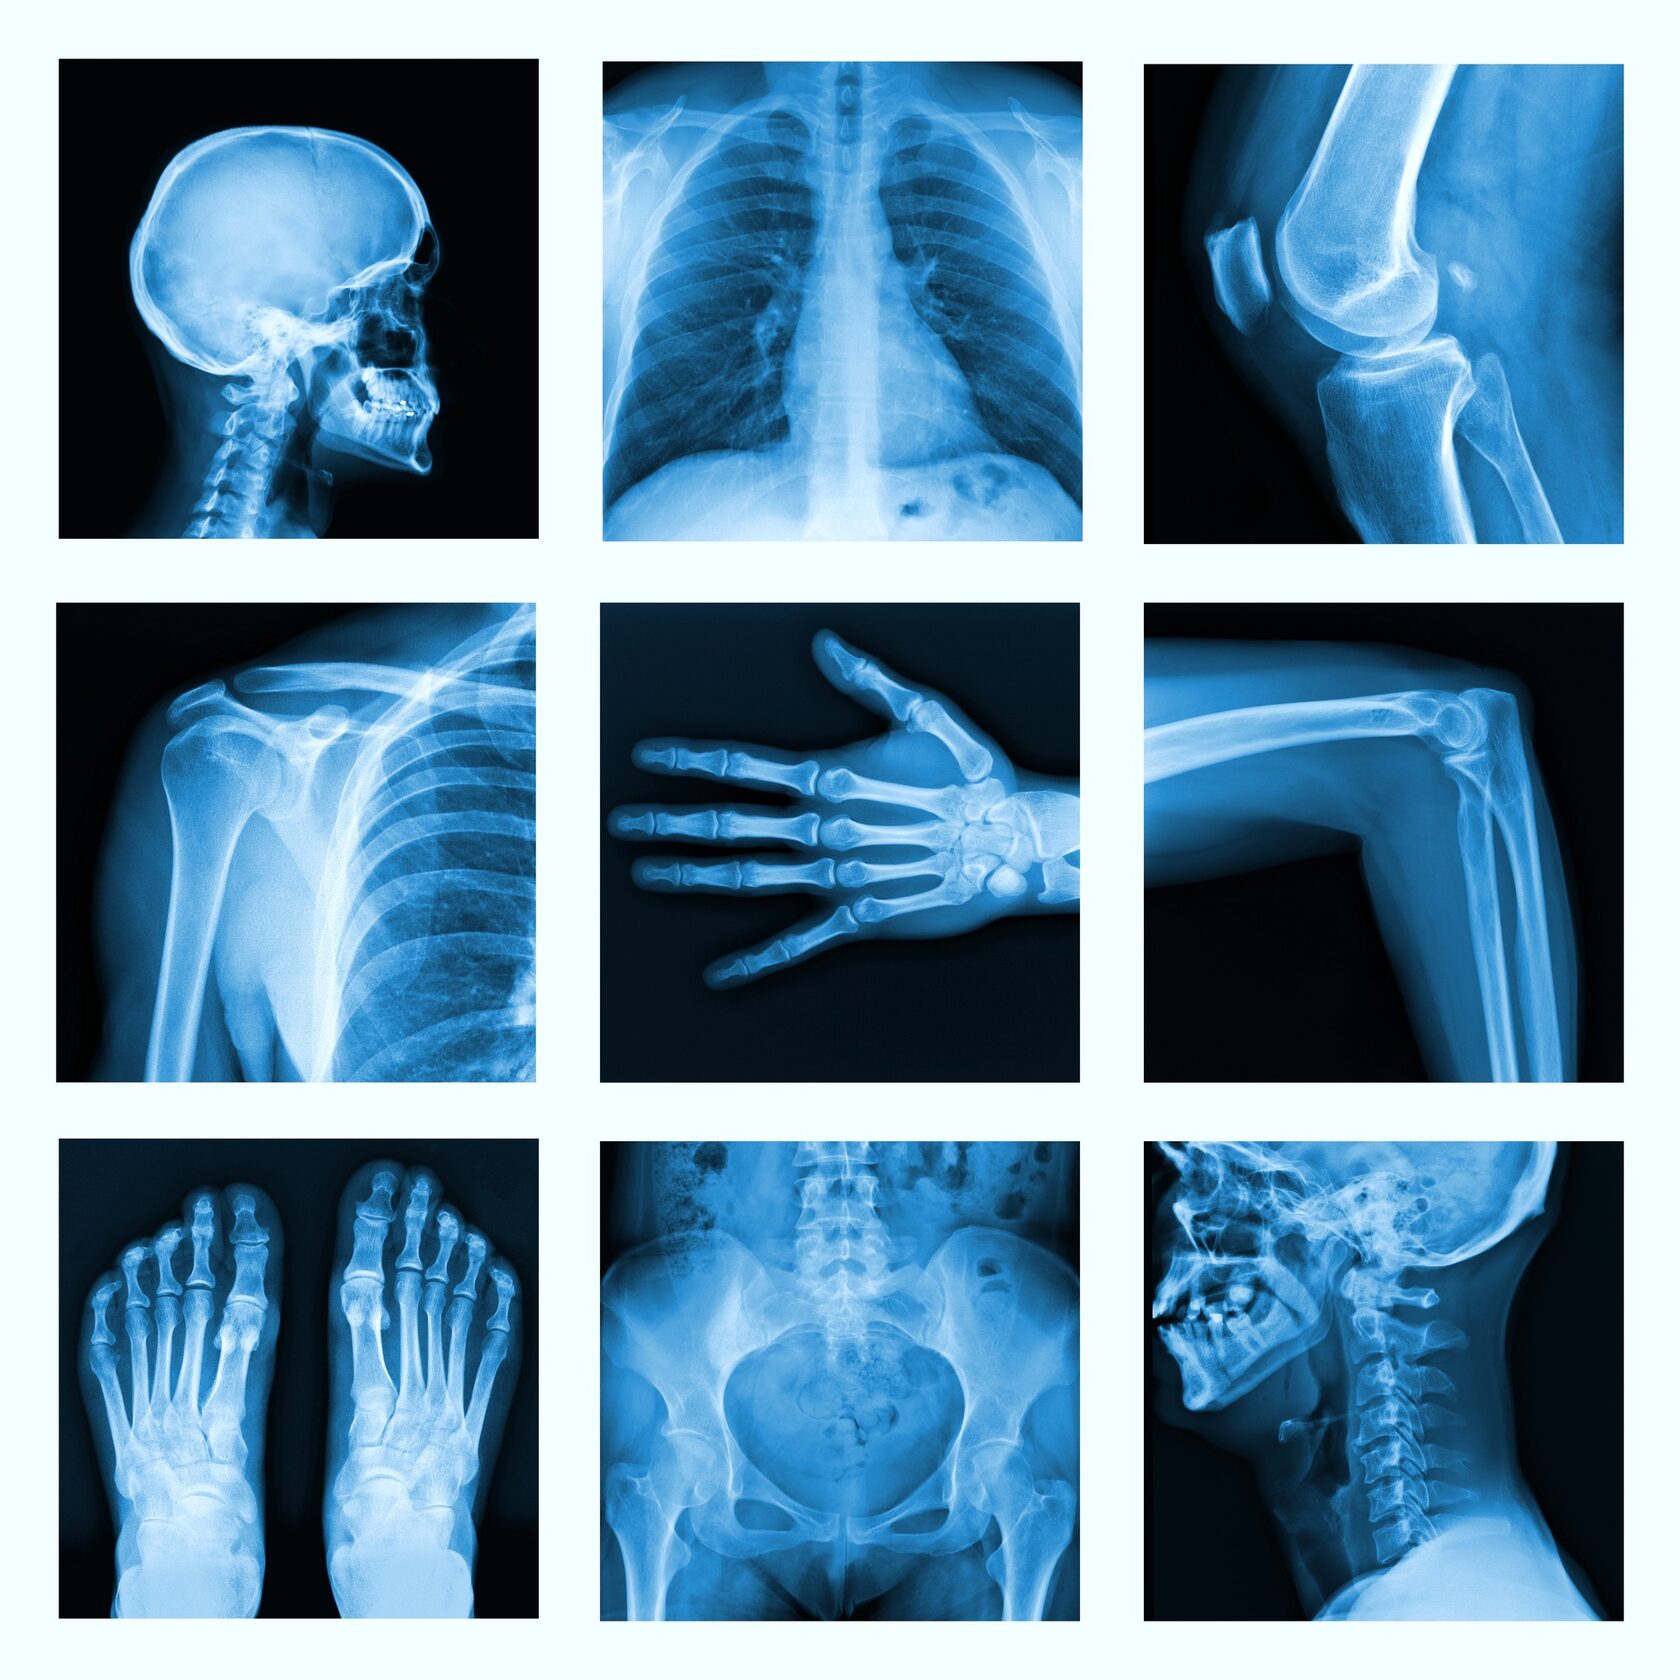

В зависимости от патологии и данных осмотра врач-травматолог может назначить пациенту дополнительные исследования: рентгенологическое, контрастную артрографию, компьютерную и магнитно-резонансную томографии, а также УЗИ[5].